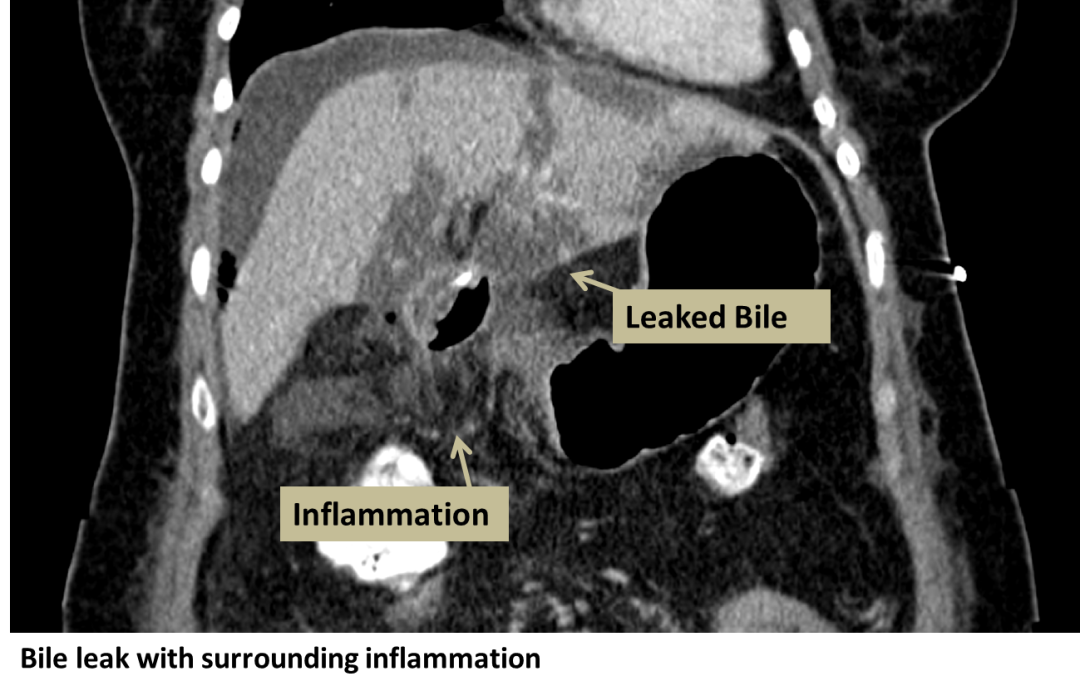

Biliary Leak Interventional Radiology UCLA Health